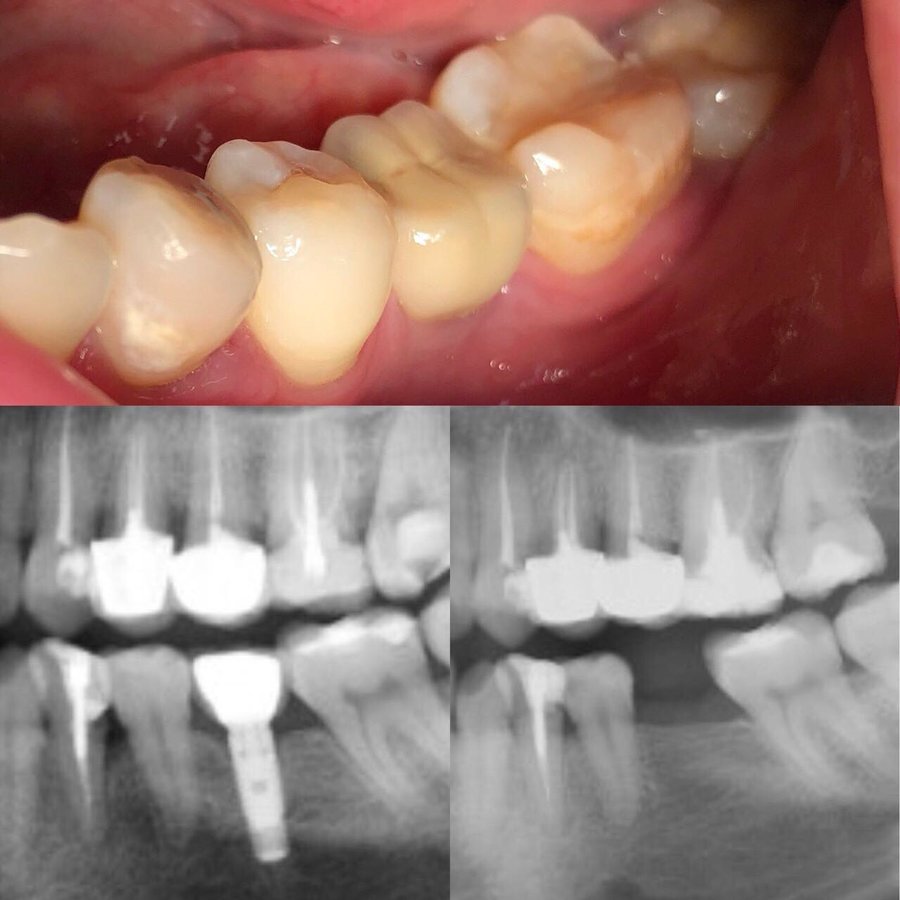

Root Canals $45

Fillings $45

Dental Implants $445

Dental Crowns $139